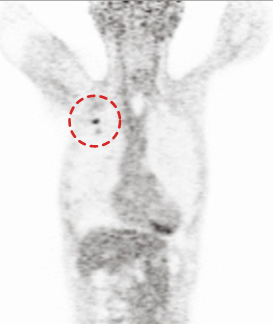

CASE #1 [lung cancer]

15 min (50%) Scan without Denoising

15 min (50%) Scan With Denoising

30 min (100%) Scan Standard